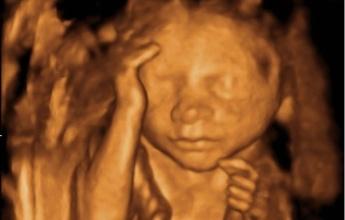

做四维彩超的时间是怀孕20-28周,在这期间,胎儿发育迅速,身长约30厘米,体重约600g,像个哈密瓜那么大。胎儿已经占据了子宫绝大部分空间,子宫内空间变得拥挤。胎儿为了适应狭窄的生存环境,只好抱住头、蜷缩着身子。

胎儿手的位置基本处于向上的状态,不是摸头,就是揉眼睛、捏鼻子、吸吮手指。这些都是他日常的一些活动,没有什么特别的。当胎儿出生以后,宝宝的手总是向上举着,呈现投降的姿势,就是因为在子宫里形成的习惯。